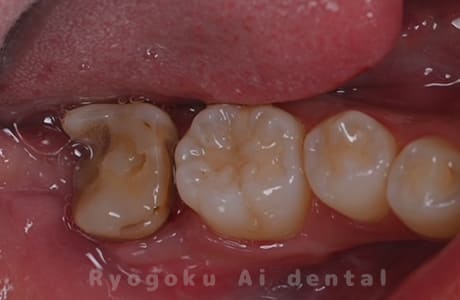

Case21

- 重度カリエス

- 治療内容

- クラウンレングスニング

- 治療費用

- 44,000円

他院で抜歯と宣告され、当医院を受診された患者様です。クラウンレングスニングを行い、保存を行いました。経過良好です。

<リスク・副作用>

手術後は痛み、腫れ、痺れ、青あざなどの副作用が生じます。痛みは痛み止めを処方しますが、腫れ、青あざは1週間程度生じる場合があります。また、部位によっては神経の走行が複雑で、痺れが残り、長期的にお薬を処方する場合があります。